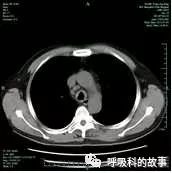

病例3患者,男性,57岁,以“咳嗽咳痰半年,气急2月,加重2周”入院。半年前出现咳嗽、咳痰,咳嗽时感胸口疼痛,血白细胞 5.1×109/L,中性粒细胞75%,血红蛋白88g/L,血小板计数 243×109/L“,诊断“缺铁性贫血”,予“力蜚能”,病情未见好转。到外院住院,骨髓细胞学检查“粒系胞浆中可见中毒颗粒,少部分有巨有样变,成熟粒细胞分叶增多”,胸部CT检查示“气管壁增厚待查”,予“曲马多胶囊、叶酸”等治疗后,复查血红蛋白 89g/L,咳嗽时胸部疼痛较前减轻出院。2个月前咳嗽、咳痰未控制,伴发气急,活动后明显,在外院诊断为“支气管哮喘急性发作”,予以 “舒利迭、万托林”治疗效果不佳,转我院治疗。既往有吸烟史20余年,平均2-3包/天,目前已戒烟10年。实验室检查:总蛋白 75.3g/L,免疫球蛋白G 24.45g/L,补体C3 2.06g/L,补体C4 517mg/L,HLA-B27 阴性;血沉 80mm/h;自身抗体ANA 1:100、SSA 阳性。肺功能显示固定性气流受限样改变(图7)。肺部气道CT三维重建示气管及主支气管壁增厚及管腔局部狭窄(图8)。诊断为复发性多软骨炎。

图8气道三维重建见气道壁弥漫增厚及管腔局部狭窄;

图9纵隔窗示气道壁弥漫增厚。